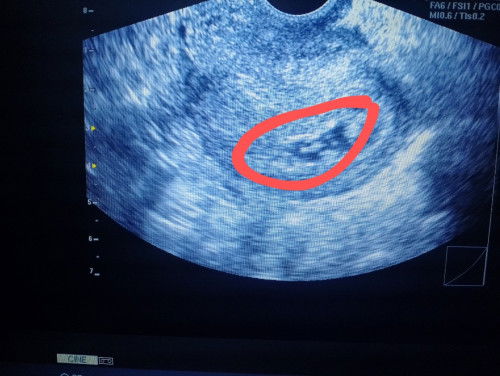

Good evening! Just want to share my first ever experience po. I was advised by my OB to come back after 2weeks to re-do the tvs. Here's the photo of my ultrasound (see attached image) There's a baby but she said that the sac is "magulo" and prolly telling us lowkey that it was a missed miscarriage. I'm scared yet want to be hopeful at the same time. I found some articles saying poor water intake can affect the result of ultrasound. The tvs was taken around lunch time—unfortunately, I didn't drink water that time since I woke up late and was in a hurry for my work after lunch too. She also said that maybe I miscounted the last day of my menstrual period as well and the baby is too tiny at the moment. (Incoming 2 mos palang raw siguro si baby) Nevertheless, please do enlighten me. There maybe someone out there who experienced this kind of incident na din. Thank you in advance and have a good night ahead!